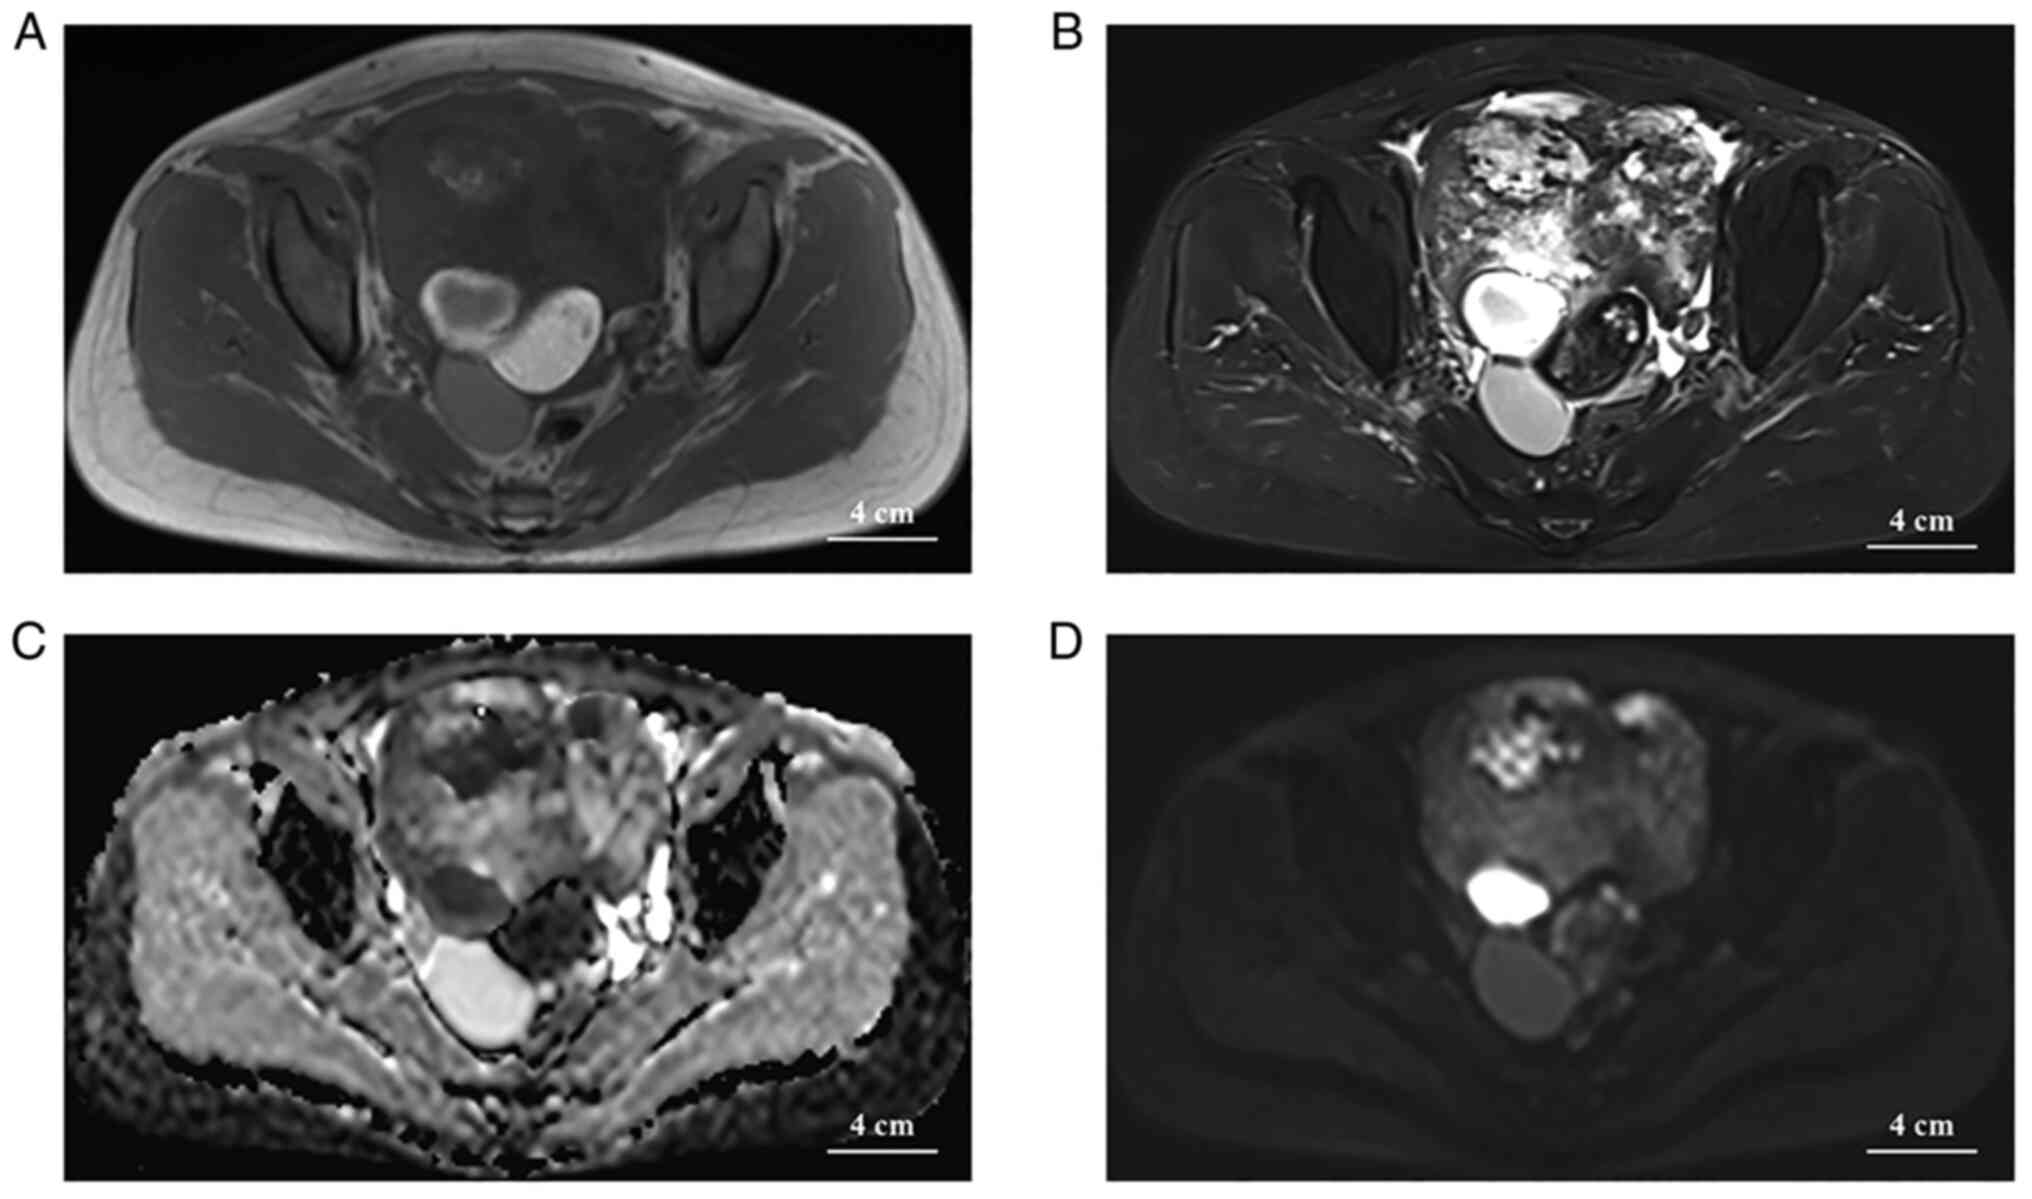

The CT scan of the pelvis revealed a large mixed-density mass of 12×11×10 cm, with organs around the lesion pushed away (Fig. 1A). The tumor parenchymal section exhibited progressive enhancement (Fig. 1B-D). A thick left uterine artery was seen supplying blood to the mass in the left posterior aspect of the entire mass (Fig. 1E). In the right posterior part of the whole mass, fluid-dense and fat-dense masses were seen and no significant enhancement was observed on enhancement CT (Fig. 1E). Finally, a large amount of pleural fluid was observed on the right side of the patient's chest cavity on the CT plain examination of the chest, while there was no fluid in the left (Fig. 1F). On MRI, a vast mixed-signal mass in the pelvis with an intact envelope was seen in the pelvis, with a predominant hypersignal on T2-weighted imaging (T2WI), a cystic necrotic area or edematous area was observed within the mass and the parenchymal portion of the mass exhibited an isosignal on T1WI and a slight hypersignal on T2WI (with the surrounding muscle tissue signal as an isosignal reference). In addition, liquid and fat signals were observed in the right back of the mass, with clear boundaries, and the fat portion of the mass had significantly lower signals on T2WI (Fig. 2A and B). The necrotic or edematous area of the cystic lesion had a hypersignal (b=1,000 sec/mm2) on diffusion-weighted imaging (DWI) and a hyposignal in the apparent diffusion coefficient (ADC), and the parenchymal portion displayed as an iso-/hypersignal on DWI and an iso-/hypersignal in the ADC (Fig. 2C and D). No enlarged lymph nodes were seen in the pelvis or groin. At the time, radiologists initially considered ovarian cystic adenocarcinoma with mature cystic teratoma and thickening of the peritoneum in both the abdominal and thoracic cavity effusion, suggesting metastasis based on the patient's age and imaging. However, subsequent thoracentesis revealed that the patient's right pleural effusion was a slightly turbid, yellowish exudative fluid with a total protein concentration of 40.3 g/l and no cancer cells were found. However, it was not possible to rule out the possibility of other malignancies and teratomas combined. After a multidisciplinary discussion, it was finally decided that the best treatment strategy was to perform surgery with intraoperative pathological frozen biopsy.

Figure 2.

(A) Axial T1-weighted MRI indicating a large mixed-signal lesion in the pelvis with a small lobulated solid cystic mass in the right posterior region, which is surrounded by a large anterior mass forming a ‘nested tumor’ pattern containing fatty nodules (arrow) with well-defined margins. (B) On the axial fat-suppressed T2-weighted image, the larger anterior portion of the entire occupying lesion displays with a mixed signal with a predominantly hypersignal, while the posterior portion of the fat nodule has a distinct hyposignal. (C) In the ADC image, the mass is predominantly hypersignal with a lamellar hyposignal. (D) The portion of the ADC image that is hyposignal appears as a slight hypersignal on DWI (b=1,000 sec/mm2) (scale bar, 4 cm).

The imaging appearance of ovarian collision tumors is dependent not only on the imaging appearance of the individual tumors of which they are composed but also on the pattern of collision. In the present case, a substantial portion of the OSST and the necrotic cystic and edematous areas were iso-intense and slightly hypo-intense on CT, respectively. The tumor signal is more uniform on T1WI because the fibrous tissue, cystic lesion and edematous part inside the tumor are hyposignal or isosignal on T1WI. By contrast, the tumor signal on T2WI is mixed and uneven, and areas of hypersignal within the tumor do not exclusively represent areas of necrotic cystic lesions but may also be sparse edematous connective tissue. The parenchymal portion of the tumor exhibited a hypersignal on DWI (b=1,000 sec/mm2), suggesting a high cell density, which is consistent with the abundance of tumor cells in the pseudolobules seen on pathology. The ADC signal of the tumor is predominantly hypersignal, suggesting to a certain extent that the tumor is benign, while the ADC value of malignant tumors is usually low, which helps differentiate it from malignant ovarian tumors. Enhanced scans indicated a marked enhancement in the solid portion in the arterial phase because of the rich vascularity of the tumor and delayed enhancement in the venous phase due to the rich collagen fiber component inside, showing an enhancement pattern similar to that of cavernous hemangioma of the liver, while the cystic region was not enhanced. A thick and tortuous uterine artery was seen on the left side of the tumor to supply it, revealing the blood-rich properties of OSST. A cystic fluid-dense and fat-dense mass was seen within the whole mass on the right posterior side, which was surrounded by a massive tumor in front. After contrast enhancement, no significant enhancement was seen in this part of the mass. The fatty part of these masses exhibited a significant hyposignal on the T2 fat suppression sequence image. In addition, ascites were observed in the periphery of the tumor, but no enlarged lymph nodes were present, which was consistent with the biological behavior of this tumor.